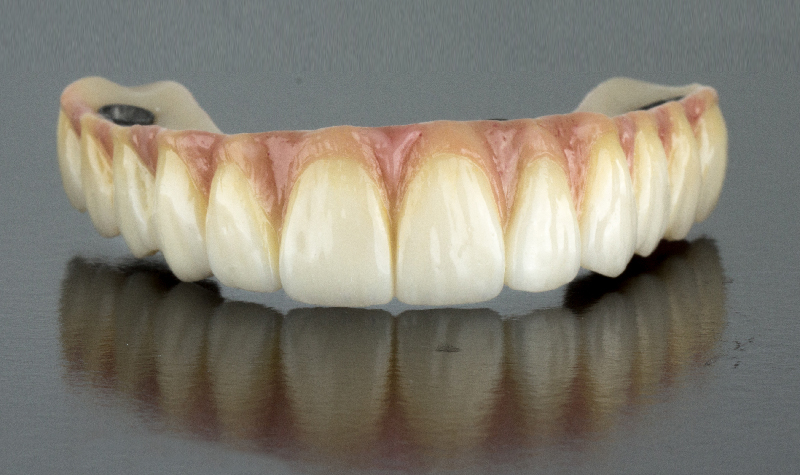

Prótesis híbrida inferior de cerámica fija sobre implantes.

Prótesis híbrida superior de cerámica fija sobre implantes.

Prótesis híbrida superior de cerámica fija sobre implantes